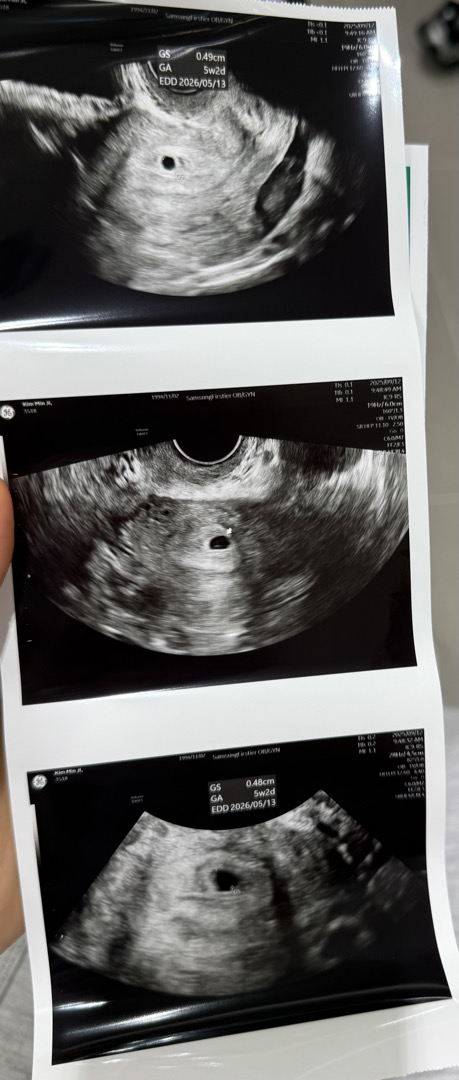

아기집 모양만 봐도 성별 대략 알 수 있다던데 정말인가요????? 초산모라 다 궁금하네요 🥹 생리일 기준으로는 5주 0일차 예상이었는데 초음파 가서 보니까 5주 2일로 계산되더라구요! 착상이 빨리 된건가요??? 엄마분들의 촉은 어떠신가요!?